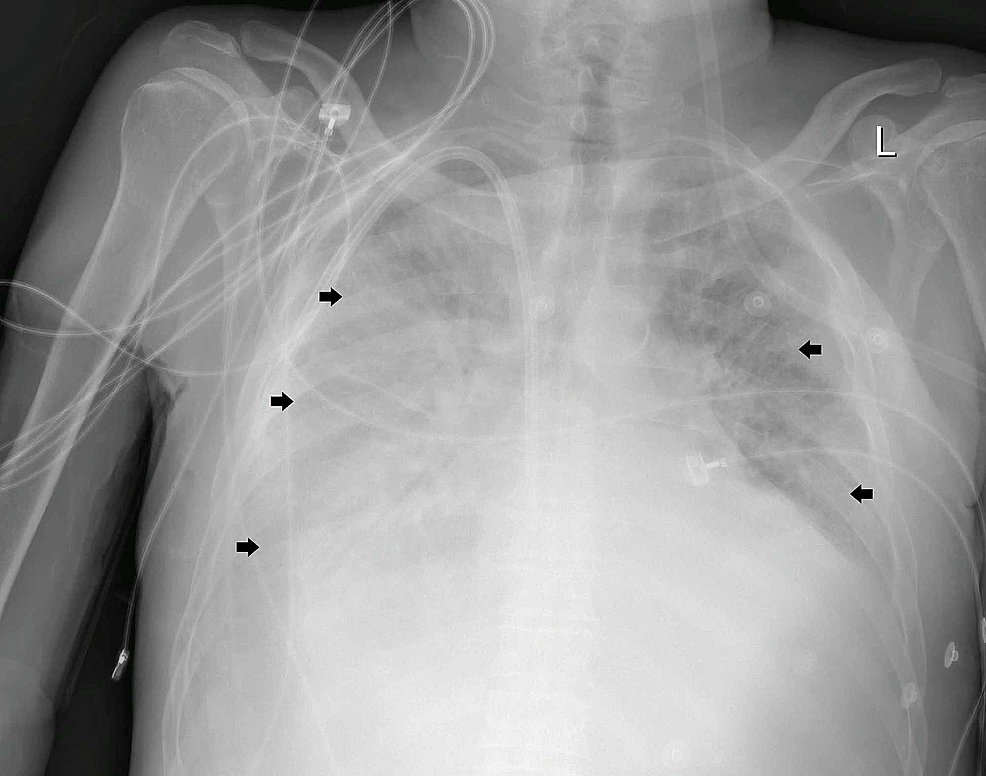

Approximately 24 hours after admission, the patient was shifted to an isolated high dependency unit for additional monitoring after further desaturation despite oxygen therapy (PaO2 / FiO2 ratio 250). An urgent portable chest x-ray revealed bilateral patchy lower lobe predominant airspace opacification more diffusely involving the right lung, and more peripherally in the left lung (Figure 1).

Common abnormal radiographic findings in the chest x-rays of COVID-19 pneumonia patients were consolidation and ground-glass opacities, with bilateral, peripheral, and lower lung zone distributions. Our patient had typical chest x-ray findings (Figure 1); thus CT-scan was not needed for diagnosis [11].